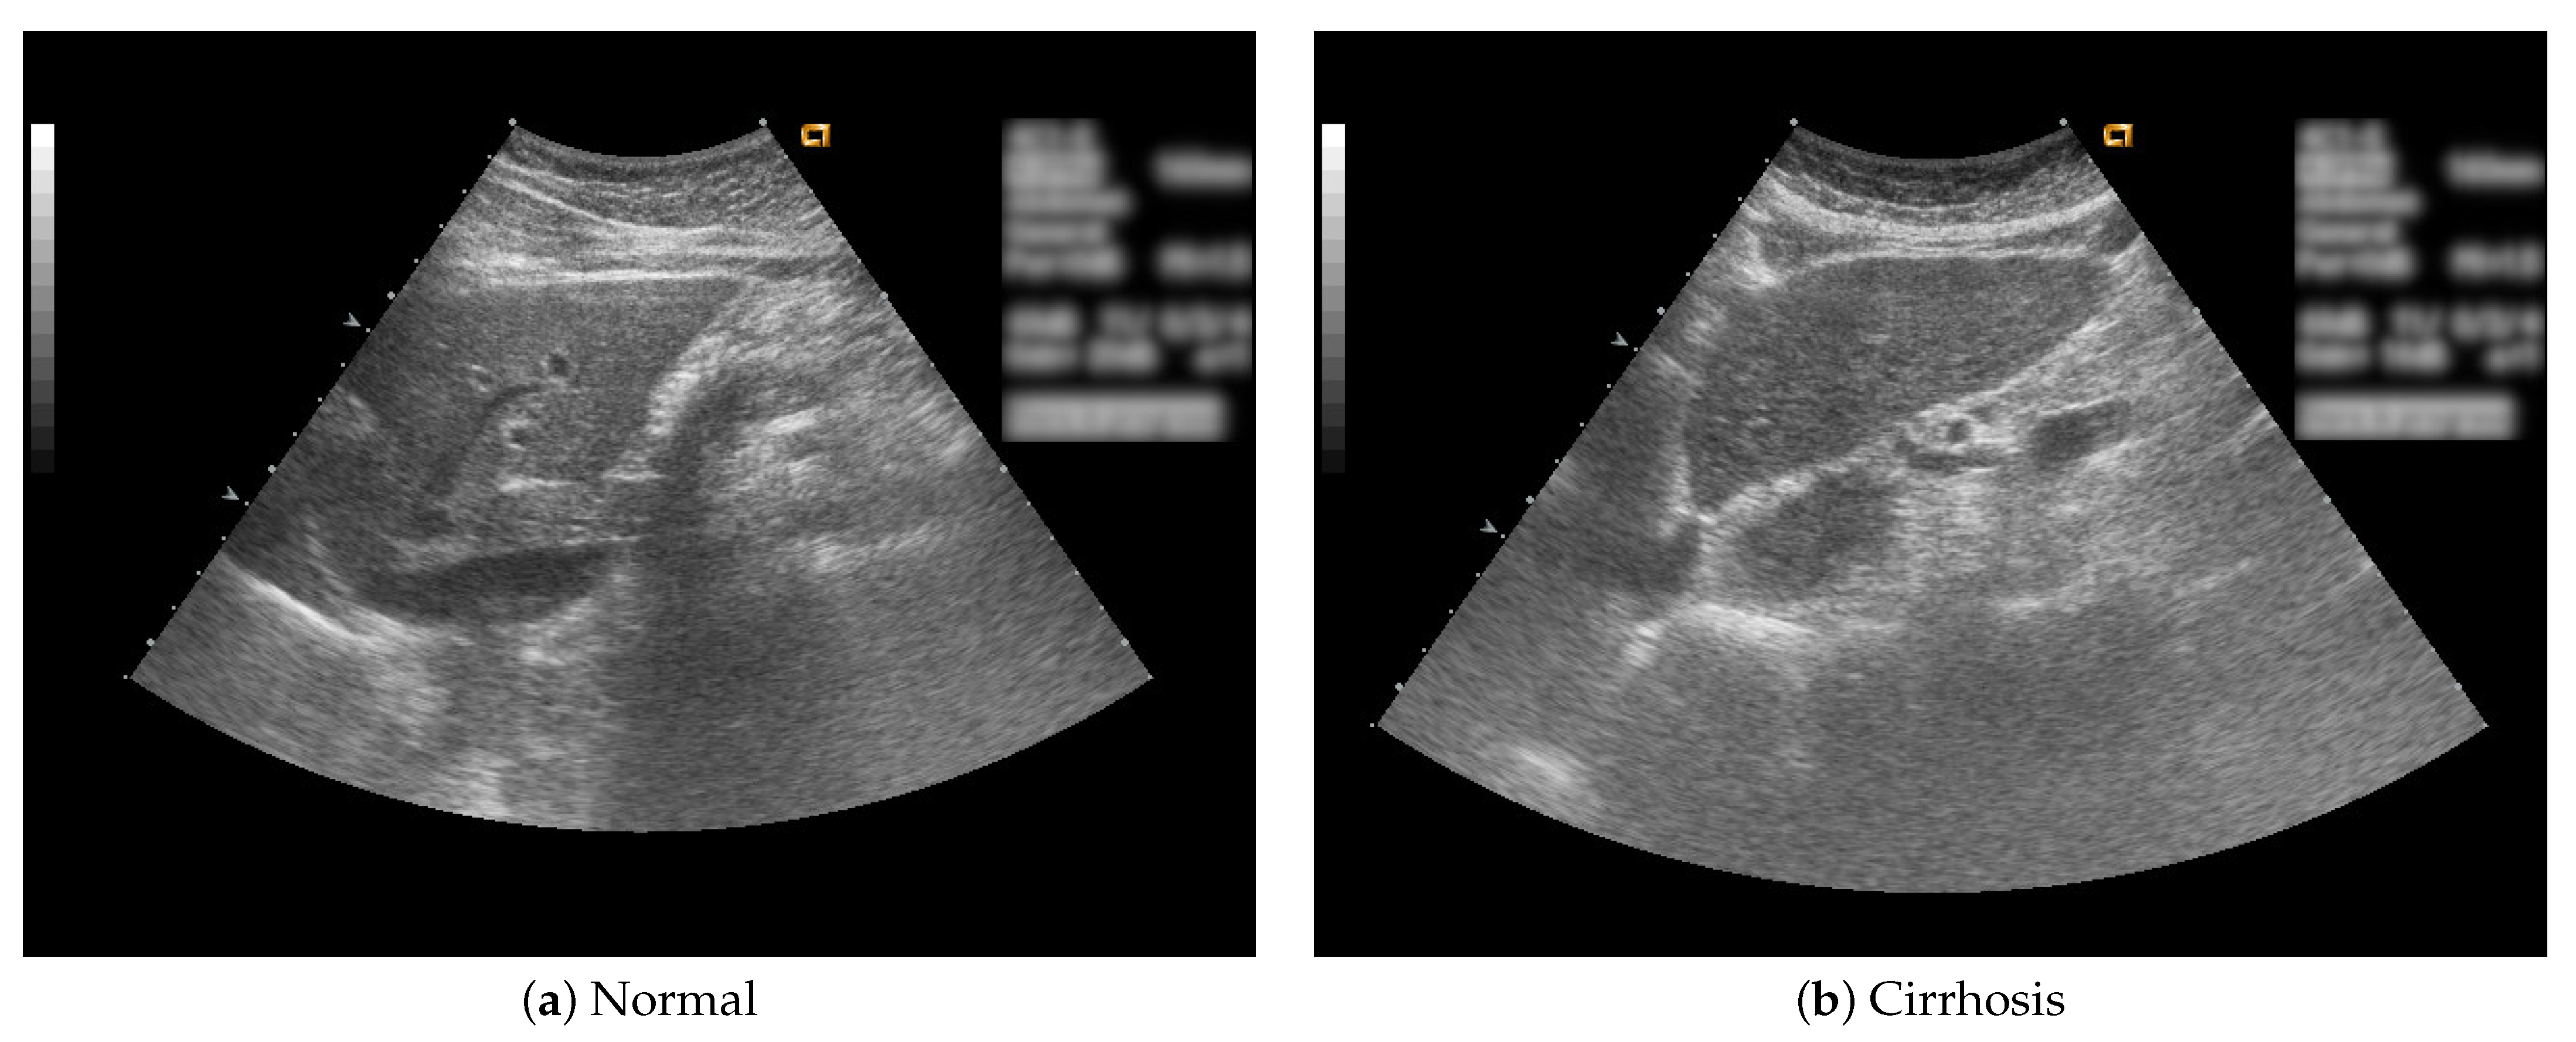

In this study, B-mode liver ultrasound imaging is focused on. B-mode ultrasound image data was provided by the collaborator. These data include 12 cirrhosis patients and 8 normal subjects. There were five ultrasound images per person. Figure 1 shows B-mode liver ultrasound images. Figure 1a,b show a normal and a cirrhosis liver, respectively. In this study, we focus on classifying regions of interest (ROIs) from the B-mode ultrasound images. Figure 2 shows examples of ROI images. The ROI images were manually cut out from the liver areas by a physician. A total of 200 normal and 300 cirrhosis ROI images were collected. Figure 2a,b show normal and cirrhosis livers. The size of each ROI image was 32 by 32 pixels. The grey level was 8 bits. Thus, the values ranged from 0 to 255. This is a typical two-class problem, normal or cirrhosis. From this figure, it seems difficult to visually classify a liver as normal or cirrhosis if one is not a physician because of noisy ultrasound images.

Figure 1.

Liver ultrasound images.